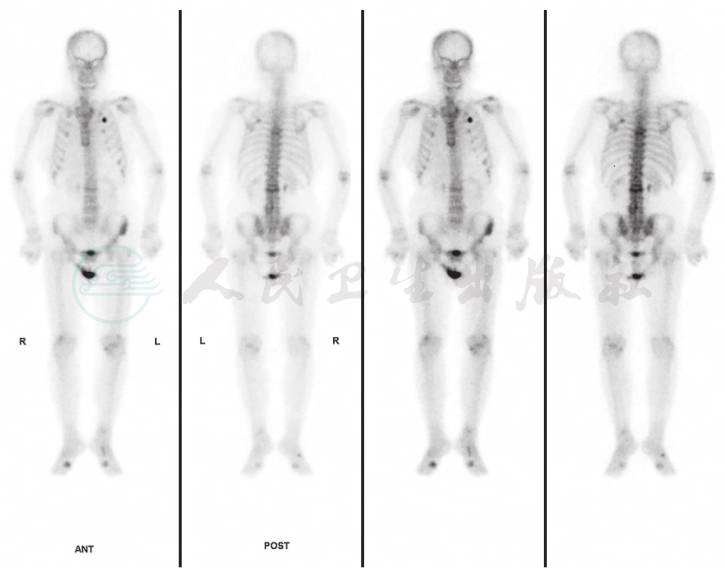

眼B超见左眼玻璃体混浊(图2)。UBM检查见中低回声巩膜隆起(图3)。对右眼巩膜肿物进行穿刺,取其内容物培养未见细菌、真菌等微生物生长。PET-CT见肋部软骨串珠样改变(图4)。

图4 患者风湿免疫科查PET-CT见肋部软骨串珠样改变

引自:主编:.同仁眼科疑难病例精析:同仁眼科临床病例讨论会1.第1版.ISBN:978-7-117-33030-5